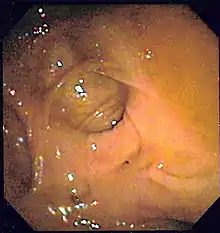

![]() | |

| A positive fecal occult blood test | |